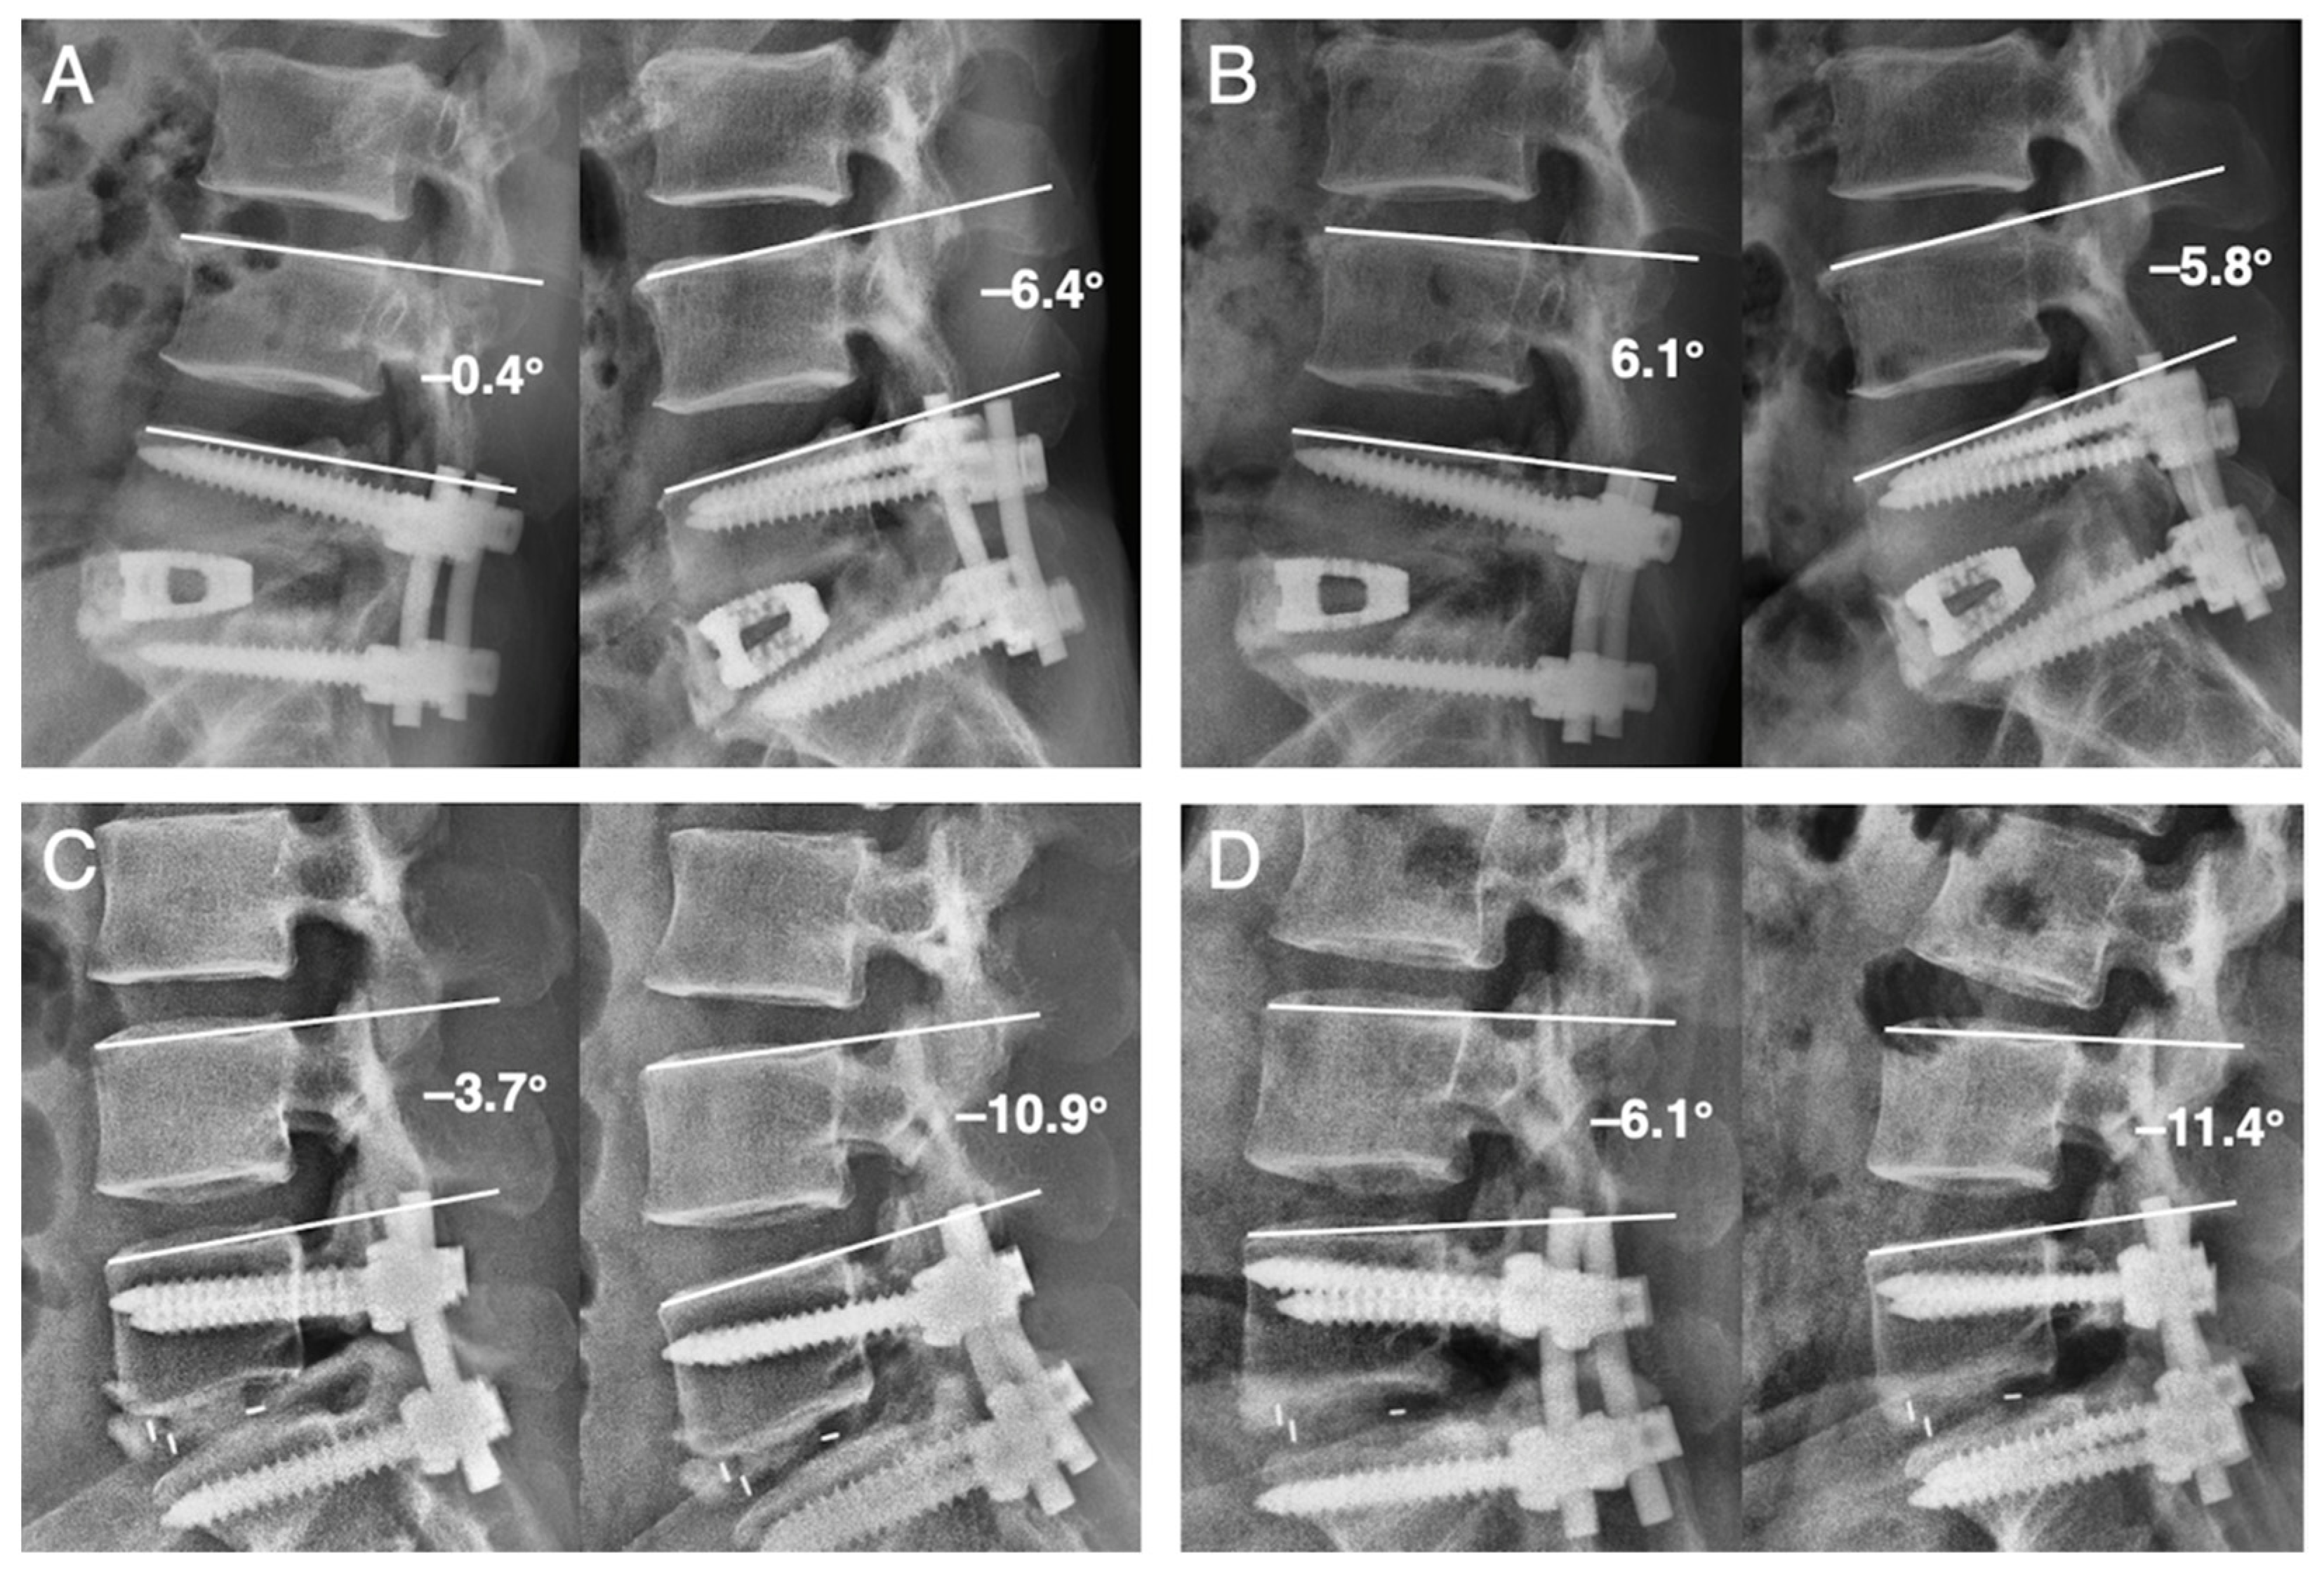

2.3. Radiological Assessment and Clinical Record

| Instability | 13 | 6 | 0.008 |

| Last FU angular m. (°) | 12.03 ± 4.25 | 10.09 ± 4.89 | 0.09 |